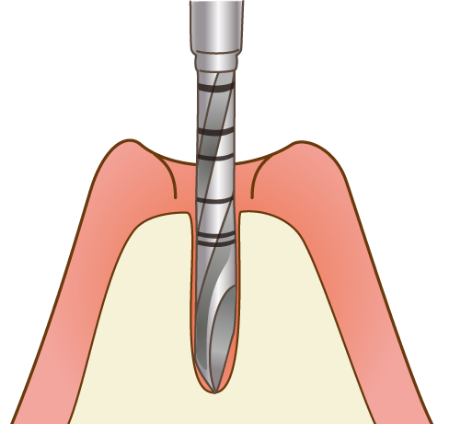

当院のインプラントは、40年以上の歴史があるノーベルバイオケア社(スイス)を使用しており、骨との親和性に優れる「純チタン」の表面に「タイユナイト」と呼ばれる表面加工が施されており、周囲の骨形成が促進されると言われています。

開院以来、年間平均130件以上、法人全体で、インプラント合計本数1,600本以上の治療実績があります。その全ての症例で、歯科用CTを使用して患者様の骨の状態を確認し、丁寧にカウンセリングを行った上で治療を行っております。